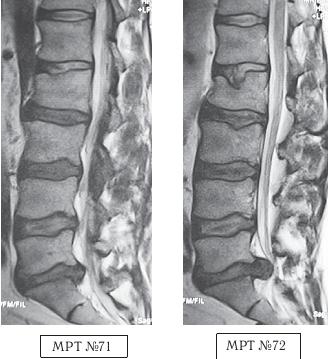

На первом МРТ № 69 отчётливо было видно, помимо протрузии, наличие эпидурита. Следовательно, этот пациент нуждался в медикаментозной терапии под контролем невропатолога, к кому и следовало бы направить больного после МРТ-обследования. В данном случае категорически нельзя было лечить методами вытяжения или мануальной терапии. Ведь при применении данных методов результат можно было легко спрогнозировать! Опять-таки это показательный случай, когда «специалисты» посылают человека на МРТ, однако оценивают снимки непрофессионально. В противном случае они могли бы составить элементарный прогноз последствий своего «лечения». Кстати, большинство подобных «специалистов» оказывают лишь единовременную помощь и не отслеживают здоровье пациента на протяжении как ближайшего, так и отдалённого периодов времени (месяцев, лет) после своего лечения. Что же касается этого случая, то не думаю, что данные специалисты сделали эти манипуляции умышленно, ради наживы на здоровье этого человека. Скорее всего — по незнанию азов вертебрологии и соответственно выбора метода лечения. Это и привело к тому, что теперь жизнь пациента значительно осложнилась, а здоровье после такой «помощи» несоизмеримо усугубилось. «Ne noceas, si juvare поп рotes» — «Не вреди, если не можешь помочь». Следующий случай свидетельствует о том, как до сих пор живы некоторые изначальные традиции американской школы «народных мануальщиков XIX века». Данный пациент, решив избавиться от болей в спине, обратился за помощью к «костоправу». Но, как оказалось впоследствии, от костоправа там было, как говорится, только одно название. Этот «специалист», американского образца XIX века, ощупав пациента, сказал, что выпал диск и что сейчас он его вправит. Положив пациента на пол (на живот), начал поочерёдно поднимать ноги, одновременно надавливая на поясницу, потом, положив на бок, провёл «скручивание». Таким образом, выполнив несколько манипуляций из «набора» обычной мануальной терапии, перешёл к «собственным разработкам». Он попросил пациента сесть на пол и вытянуть вперёд ноги, а поясницу прогнуть назад. Потом начал резкими, сильными толчками давить ему на плечи. Затем, попросив пациента подняться и, обхватив его руками под мышками, приподнял и сильно встряхнул. После данных манипуляций этот «специалист» по-деловому объявил, чтобы пациент пришёл на следующий день ещё для одного такого же сеанса. После второго сеанса боли у пациента усилились. Он обратился в районную больницу. Участковый травматолог направил больного на МРТ. Но вопреки здравому смыслу пациент отправился с результатами обследования (МРТ № 71) не к травматологу, а опять к тому же «костолому». Тот, внимательно посмотрев снимки, сказал, что ему «всё ясно», грыжа межпозвонкового диска «выпала вовнутрь, в живот» и что «обычно хватает одного-двух сеансов, но тут дело серьёзное и просто необходимо провести ещё один, а может и два сеанса». Пациент, по наивности своей, согласился. Всё повторилось как и в первые два раза, только этот «специалист» значительно усилил силу своего воздействия, когда посадил его на пол и начал толчками давить на плечи, очевидно, чтобы диск уж точно «вышел из живота и зашёл куда надо». Это называется: «сила есть, ума не надо». После нескольких таких толчков пациент почувствовал резкую боль («как разряд тока»), прошедшую от копчика до головы, ноги онемели. Через несколько дней у данного больного развились тазовые нарушения. Сделали повторное МРТ № 72. Результат более чем удручающий: компрессионный перелом тела позвонка LII, секвестрированная грыжа межпозвонкового диска в сегменте LV-SI, абсолютный стеноз спинномозгового канала.

На МРТ № 71 наблюдается сглаженность физиологического лордоза, грыжа межпозвонкового диска в сегменте LV—SI, спондилёз на том же уровне, множественные грыжи Шморля, стеноз. На МРТ № 72 наблюдается помимо всего выше перечисленного ещё и компрессионный перелом тела позвонка LII и секвестрированная грыжа межпозвонкового диска в сегменте LV—SI, абсолютный стеноз спинномозгового канала. ![]() На МРТ № 73 — увеличенный фрагмент МРТ № 71 на уровне сегмента LI—LII, на котором наблюдается травма замыкательной пластинки LII позвонка, как следствие первых двух сеансов у этого «специалиста». На МРТ № 74 наблюдается увеличенный фрагмент МРТ № 72 на уровне сегмента LI—LII, на котором наглядно видны последствия третьего сеанса «вправления диска», и как следствие — компрессионный «пролом» тела позвонка LII и его замыкательной (гиалиновой) пластинки и внутренний разрыв межпозвонкового диска. Причина этой трагедии в элементарной безграмотности, причём не только того «аборигена-специалиста» образца XIX века, а и самого пациента. Ведь порой даже элементарные знания или хотя бы наличие здравого смысла одной из сторон способны уберечь человека от совершения роковой ошибки, повлекшей за собой тяжёлые последствия. Вот ещё один аналогичный случай с той лишь разницей, что такого же уровня «специалист», проводивший схожие манипуляции с пациенткой, именовал себя не «костоправом», а «мануальным терапевтом». Но здесь как в математике: «от перемены мест слагаемых значение суммы не меняется». ![]() На МРТ № 75 наблюдается состояние поясничного отдела позвоночника после нескольких месяцев лечения методом вытяжения: сглаженность физиологического лордоза, стеноз спинномозгового канала, грыжа межпозвонкового диска в сегменте LIV-LV, эпидурит на данном уровне, снижение высоты межпозвонкового диска в сегменте LV-SI вследствие развития в нём дегенеративно-дистрофического процесса, жировая дегенерация в телах смежных позвонков данного сегмента, спондилёз на данном уровне. На МРТ № 76 наблюдается состояние поясничного отдела позвоночника той же пациентки после нескольких сеансов лечения у мануального терапевта: кифотизация физиологического лордоза, абсолютный стеноз спинномозгового канала, грыжа межпозвонкового диска в сегменте LIV-LV, эпидурит на данном уровне, снижение высоты межпозвонкового диска в сегменте LV—SI, компрессионный перелом тела позвонка LV, усугубление дегенеративных процессов в сегменте LV—SI. Следующий пример наглядно показывает, как уже два разных мануальных терапевта участвовали в лечении пациента и, соответственно, какие результаты показали МРТ-обследования. Весной 2001 года данный пациент почувствовал боли, скованность в поясничном отделе позвоночника. Друг посоветовал «хорошего мануальщика». После первого курса (12 сеансов) пациент, по его выражению, «просто летал», однако через два месяца «крылья подрезало». Прошёл ещё курс мануальной терапии, стало легче, но боли полностью не прошли. Осенью того же года повторил курс лечения, боли только усилились, однако лечение продолжил. |